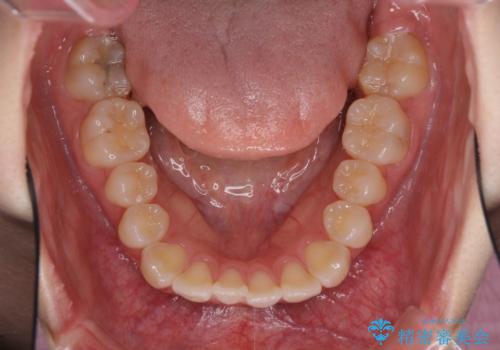

前歯にデコボコがあり、口元がやや突出した印象があったため、IPR(歯と歯の間を削る)と親知らずを抜歯した上での歯列全体の後方移動をメインに、インビザラインを用いて矯正治療を行うこととしました。

年に一度、夏休みの時期にしか帰国できないため、帰国のタイミングに合わせてマウスピース交換スケジュール治療計画としたため、3年半という期間を要しました。

留学先でもしっかりとマウスピースの装着を実践してくださったので、ご本人の満足のいく仕上がりとなりました。